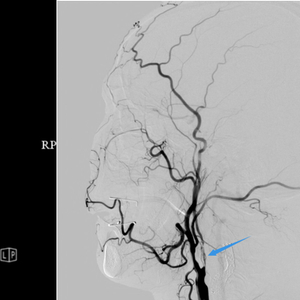

在亲戚的推荐下,他慕名找到广州医科大学附属第一医院神经内科刘磊医生,经过详细的彩超及造影检查,刘磊医生发现,患者右侧颈动脉重度狭窄,已经被堵掉了90%,而且可以看到狭窄段呈蜂窝状血流,这就意味着不单纯有斑块,还伴有活动性血栓,“这种情况下是不建议做介入手术,如果继续放支架,有可能会导致血栓跑到远端去,更容易发生脑梗的风险。”

从神经内科的角度判断,介入手术不是最优选择,刘磊医生邀请血管外科王海洋主任团队前来会诊讨论,结合影像学检查报告来看,患者右侧颈动脉几乎都被斑块及血栓堵住,远端血管极细,血流速度明显减慢,需要尽快开通血管,以免造成更严重的后果。

“我们一边探查一边取栓,既要保证斑块血栓的完整取出,又要尽可能缩短右脑缺血的时间。”参加手术的血管外科副主任医师岳劼表示,尽管手术存在一定的难度,特别是远端几乎进入颅内血管,但是,王海洋主任带领团队技艺娴熟、配合默契,凭借丰富的手术经验,颈动脉阻断不到30分钟就完成了血管重建,一举将斑块和血栓取出,再将这条颈动脉血管小心翼翼地进行吻合成形手术,整台手术一个多小时就顺利完成。术后造影显示,汩汩血流在血管内畅通无阻,解除了龚大爷的颈动脉“危机”。